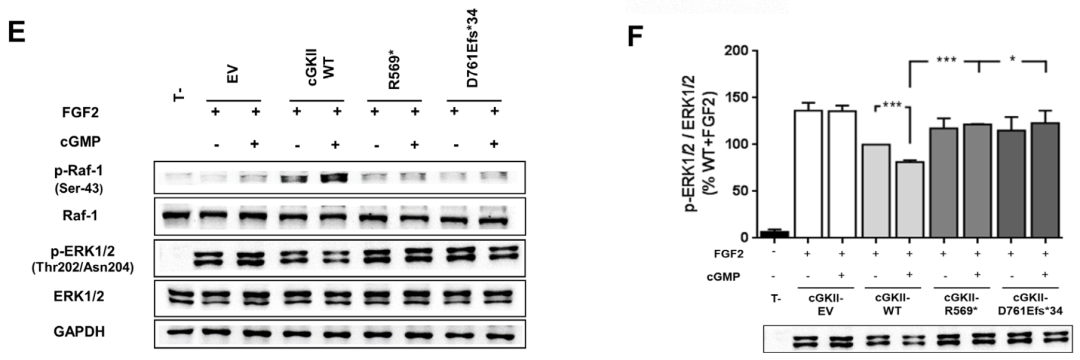

为了从功能上证实新发现的p.Asp761Glufs*34变异的致病性,我们首先用Western blot分析了cGKII的表达。以先前鉴定的p.Arg569*突变作为阳性对照,在这两个突变中,cGKII被检测到的大小与预测的大小一致,尽管与野生型相比,cGKII的水平显著降低 (≥80%)。接下来,我们通过分析p.Asp761Glufs*34突变体诱导Raf-1在Ser-43和ERK1/2磷酸化的能力,评估了它是否能够抑制FGF2诱导的MAPK通路。结果显示,p.Asp761Glufs*34突变体未能在Ser-43处磷酸化Raf-1,因此降低了FGF2诱导的ERK1/2磷酸化,这与p.Arg569*变体的结果相似。

PRKG2变异对cGKII蛋白水平/MAPK通路调控的影响